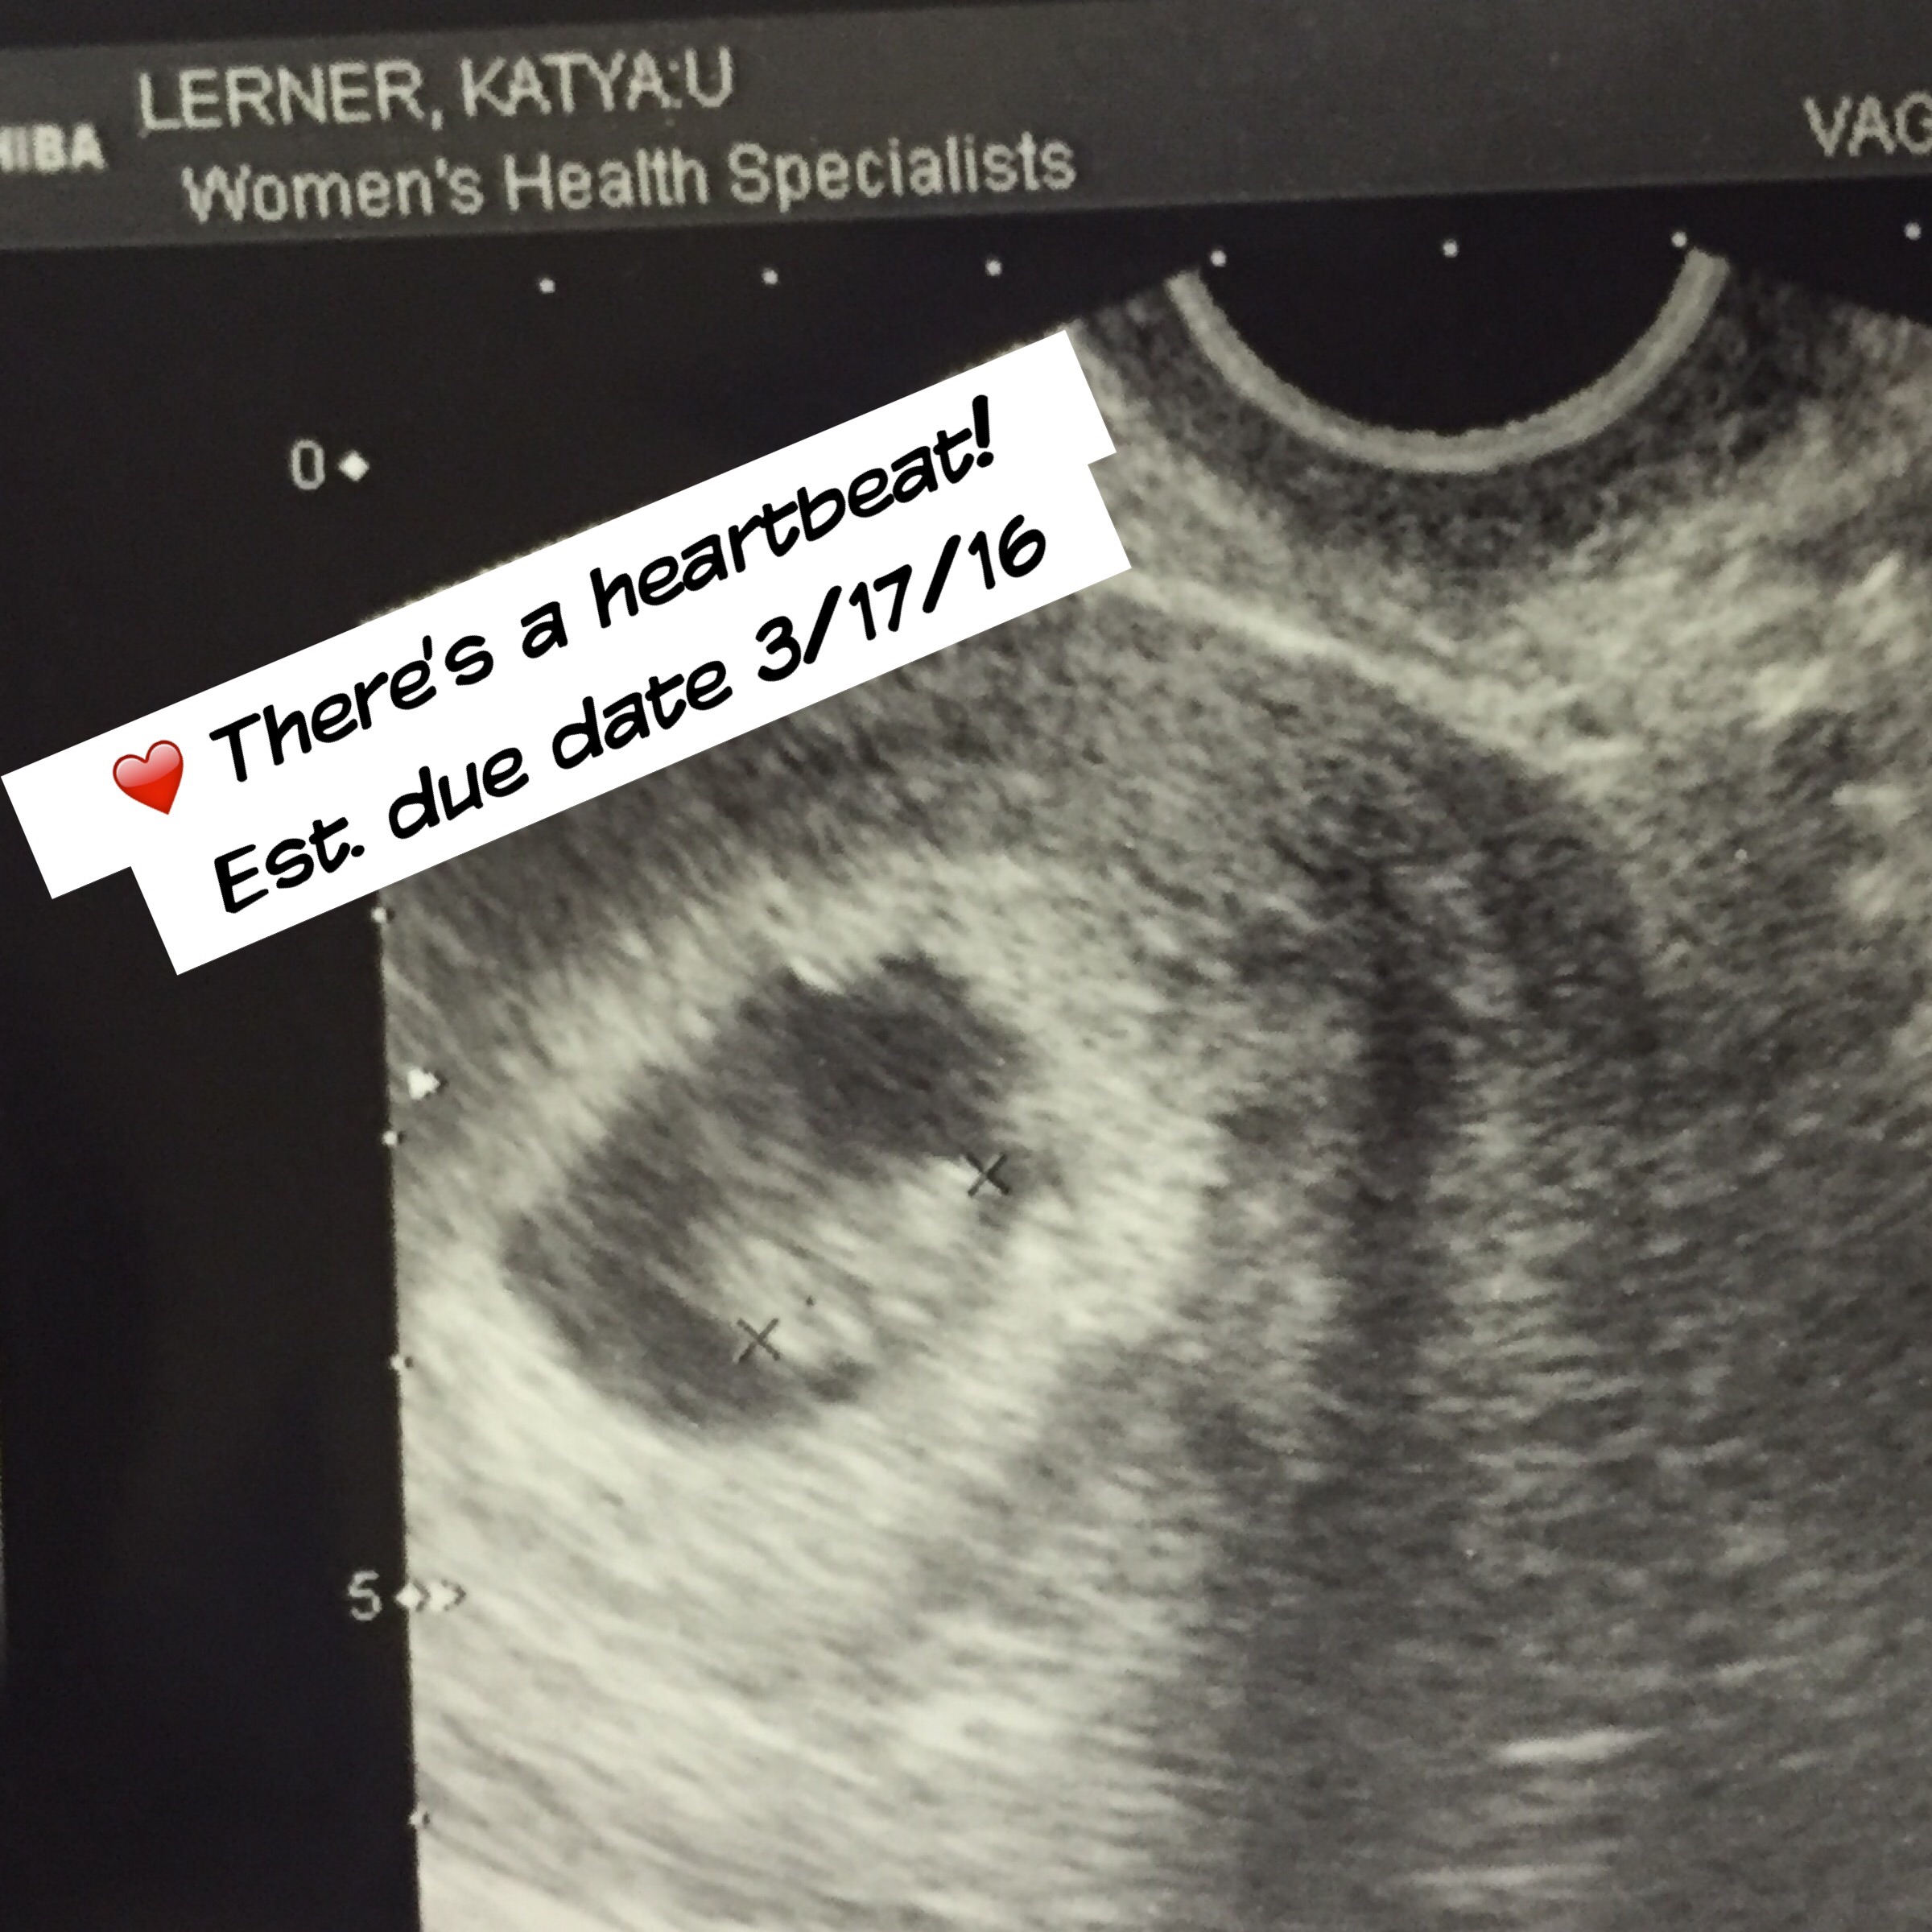

• This actually did happen to me. Got a positive pregnancy test toward the end of June, went in to see my doctor July 10 and had an U/S the next day. Well, the doctor told me that according to the due date calculator, I was 8 weeks along but at the U/S all we saw was an empty sac, and the result was that I was only 4 weeks along. The doctor stressed me out by saying, "Well, maybe you ovulated late or the pregnancy isn't viable. Call us if you start bleeding." Just went in for another U/S this weekend, and the baby was there with a heartbeat, and I'm 7 weeks along. So, it is possible that you're just not as far along as you thought! Good luck to you!!

• Thank you! I'm happy that you finally got to see the heartbeats and baby! That's encouraging, I feel great no bleeding or cramping. My doc hasn't given me a edd. First Ultrasound were we saw the sac they said it was to small to measure...second one on Thursday I think he was more concerned that the sac was empty then measuring. We can't go off of my mens cycle cause I'm breastfeeding...so yet another thing that's stresses me out not knowing how far along I am.

• I had my bloods come back at 28,820 (nearly the same as yours) and had a scan the next day and they could only see the sac. Fast forward two weeks (this monday just been) and repeat scan shows embryo complete with heartbeat! Dont worry too much about what the numbers are as long as they are rising! Good luck!